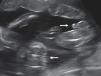

Determination of amnioticity is difficult until 8 weeks of gestation. Before that time the amnion is still too close to the embryo and is identifiable in only 50% of the cases.9 The amnions appear as thin echogenic membranes surrounding the two embryos inside the celomatic cavity (Fig. 3).

Lack of visualization of the amniotic membranes after 8 weeks allows the diagnosis of monochorionic monoamniotic twins. In this case the number of yolk sac seen may be one or two depending on the timing of cell division.10